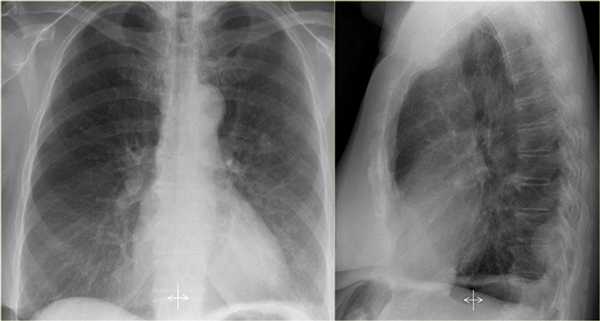

Ателектаз средней доли правого легкого.

- Симптом силуэта — нечеткие границы правых отделов сердца.

- Трехгранные изменения высокой плотности, визуализирующиеся на боковой рентгенограмме, являются результатом ателектаза средней доли правого легкого.

При ателектазе средней доли правого легкого подъем диафрагмы навсегда значительно выражен.